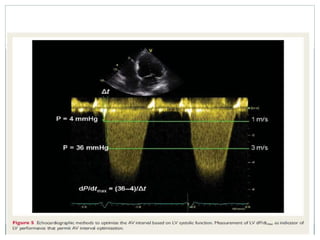

LV dp/dt

 The measurement of the LV dP/dt max provides information on LV

contractility.

 Non-invasive measurement of this parameter is performed on the

continuous-wave Doppler spectral signal of the mitral regurgitation.

 First, the time difference between two points of the spectral signal is

measured (usually between 1 and 3 m/s time points). Then, the pressure

gradient between these two points is calculated according to Bernoulli

equation.

 The optimal AV interval corresponds to the highest value of LV dP/dtmax